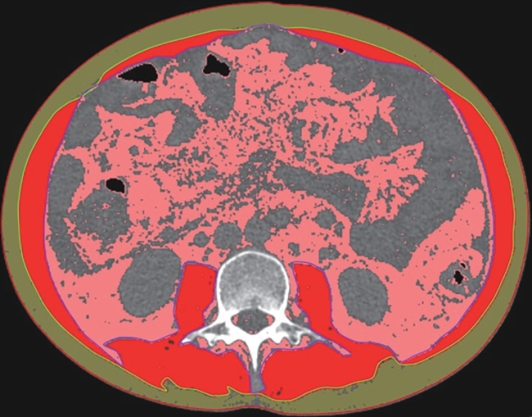

Value of internal stratification analysis of abdominal wall muscles in predicting complications after orthotopic liver transplantation

Xin SHI, Chongxiao LIANG, Bei ZHANG, Jiping WANG

2025, 41(2): 314-321. DOI: 10.12449/JCH250218

Abstract(741) HTML (353) PDF (3265KB)(54)

Abstract:

Objective  To divide the muscle into different subzones according to different density ranges using the stratified analysis on the basis of myosteatosis, and to investigate the effect of muscle density changes on complications (Clavien-Dindo grade ≥Ⅲ) after orthotopic liver transplantation (OLT).  Methods  A retrospective analysis was performed for the medical records of 145 patients who underwent OLT in The First Hospital of Jilin University from May 2013 to September 2020, and with the plain CT scan images of the largest level of lumbar 3 vertebrae of each patient as the original data, Neusoft Fatanalysis software was used to measure related muscle parameters. The independent-samples t test was used for comparison of normally distributed continuous data between two groups, and the Mann-Whitney U test was used for comparison of non-normally distributed continuous data between two groups. The chi-square test or Fisher test was for comparison of categorical data between two groups. RIAS software was used to extract clinical features and perform analysis and modeling, and three machine learning models of logistic regression (LR), support vector machine (SVM), and random forest (RFC) were constructed. The receiver operating characteristic (ROC) curve, the calibration curve, and the decision curve were plotted for each model to calculate the area under the ROC curve (AUC), sensitivity, specificity, precision, F1 score, and accuracy.  Results  The three machine learning models of LR-C, SVM-C, and RFC-C were established based on the 7 clinical features before muscle stratification analysis, among which the RFC-C model had an AUC of 0.803, a sensitivity of 0.588, and a specificity of 0.778 in the test set. Among the models of LR-CS, SVM-CS, and RFC-CS established based on the 16 clinical features after muscle stratification analysis, the LR-CS and SVM-CS models had an AUC of 0.852 in the test set, with a sensitivity of 0.765 and 0.706, respectively, and a specificity of 0.889 and 0.926, respectively. Comparison of the AUC, sensitivity, specificity, precision, F1 score, and accuracy of each model in the test set before and after muscle stratification analysis showed that there were improvements in the parameters of the predictive model after muscle stratification analysis. Comparison of the decision curves and calibration curves of each predictive model showed that the LR-CS and SVM-CS models had good efficacy in predicting postoperative complications (Clavien-Dindo grade≥Ⅲ) in OLT patients.  Conclusion  On the basis of myosteatosis, the division of the muscle into different subzones according to different densities using the stratified analysis has a certain value in predicting postoperative complications in patients with OLT.